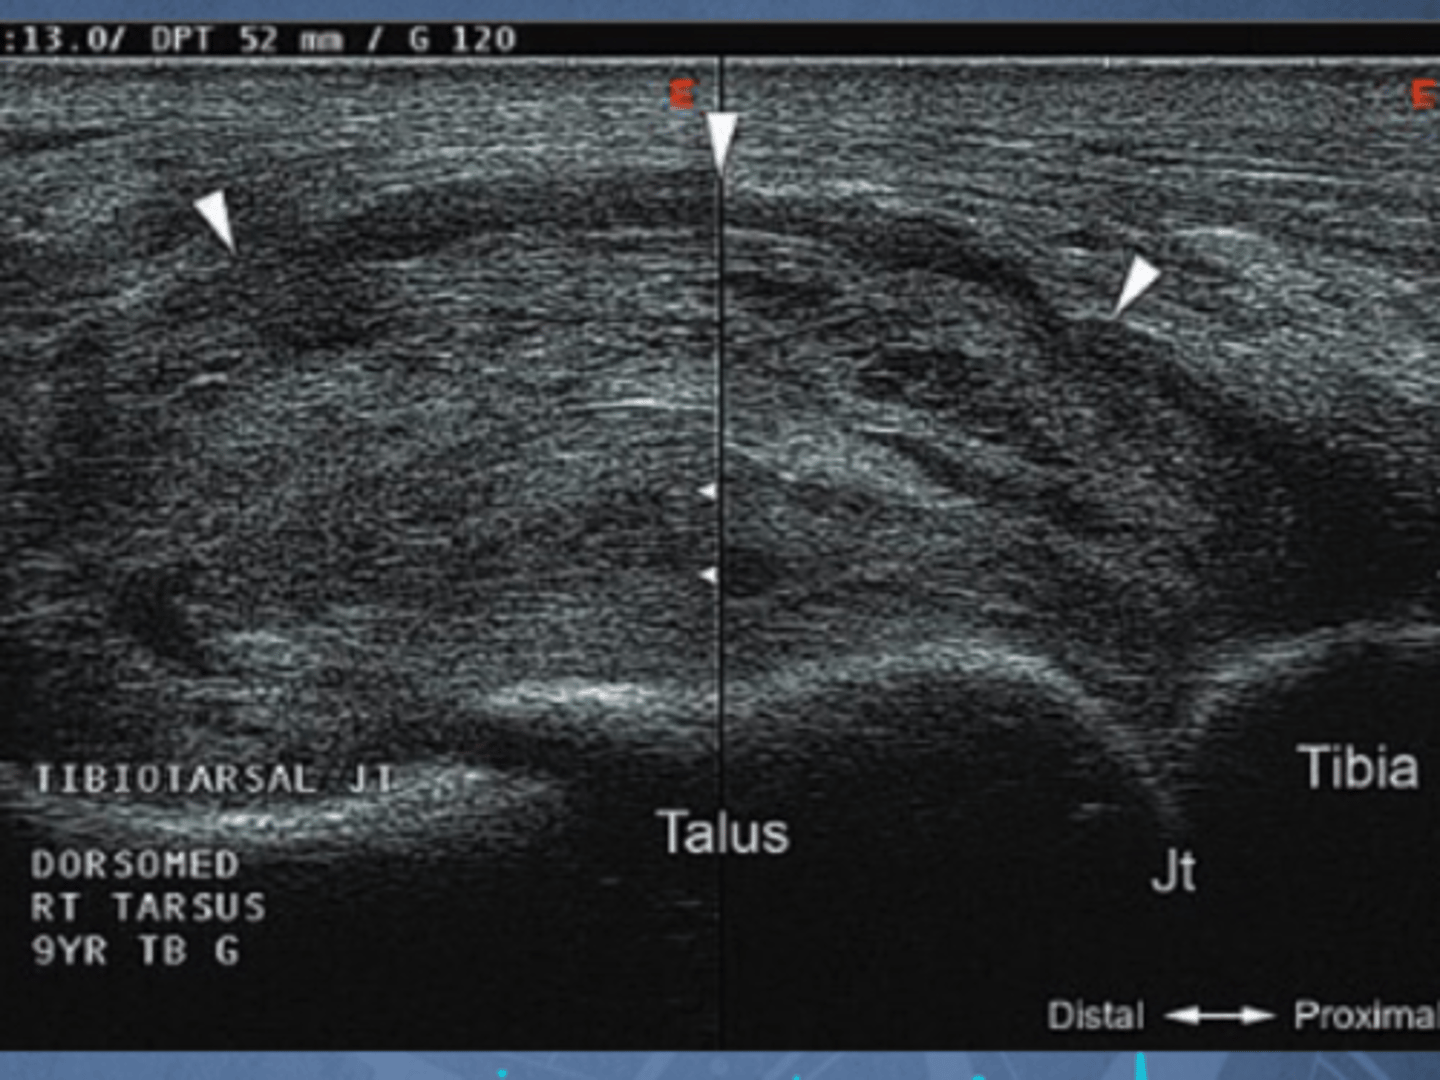

Joint effusion/ infection - fibrin and fluid pockets seen

What is the u/s identifying?